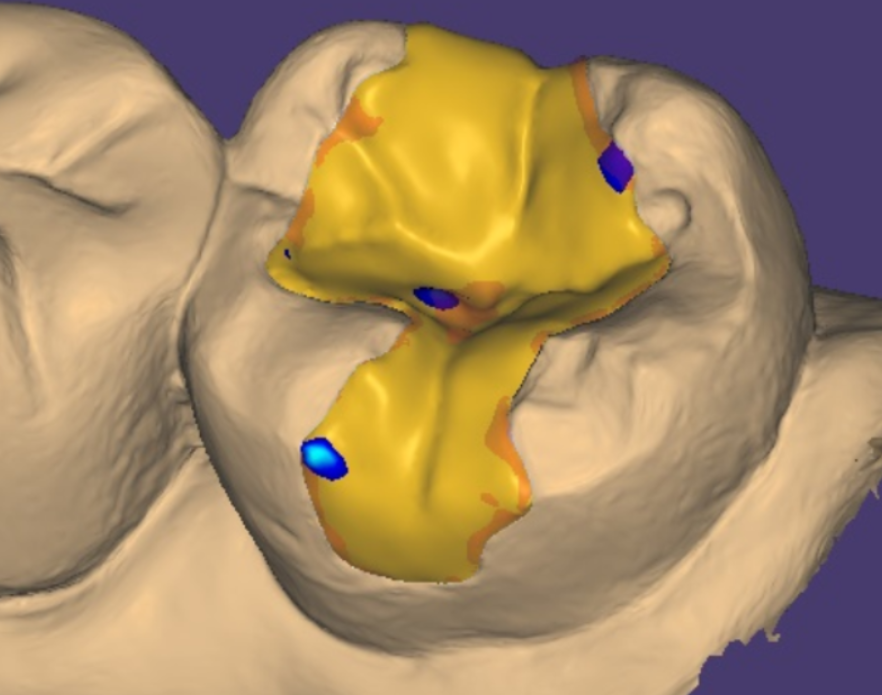

디지털 스캔을 통해 얻은 자료를 바탕으로 보철물을 설계하는데

이 과정은 매우 정밀합니다.

환자분 구강에 FIT하게

딱! 맞춰 제작됩니다.

디지털 스캐너로 뽄 뜨고

3D 프린터를 활용하여 원내에서 제작합니다.